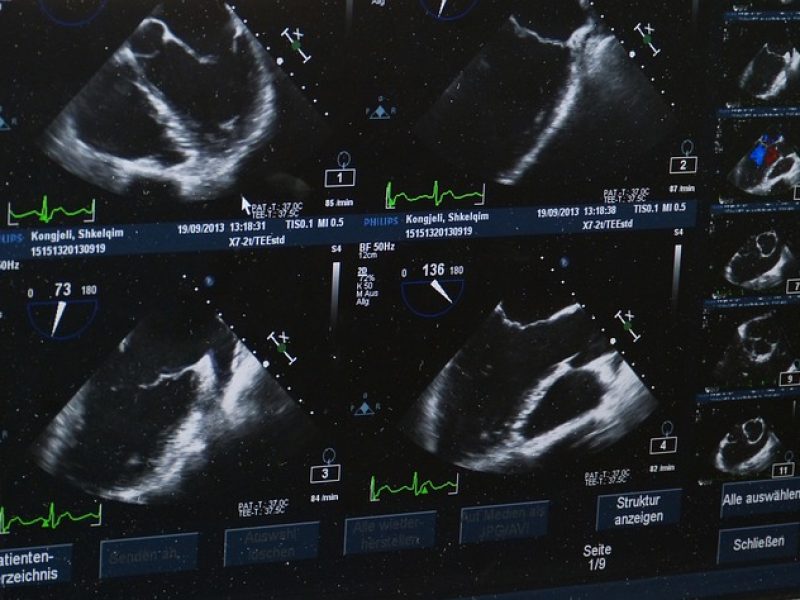

L’échographie abdomino-pelvienne peut prendre 5 à 20 minutes. Après avoir été installé sur une table d’examen, le patient expose la région à examiner. Un gel conducteur est appliqué sur la peau pour faciliter le passage des ondes ultrasonores. Le radiologue utilise une sonde pour capturer des images des organes internes en déplaçant doucement l’appareil sur la peau. Pendant l’examen, le patient peut être invité à changer de position ou à retenir sa respiration pour améliorer la qualité des images. Les résultats sont analysés en temps réel, et des images sont enregistrées pour une interprétation ultérieure. L’échographie abdominale et pelvienne est non invasive et généralement bien tolérée, ne nécessitant pas de récupération spéciale après l’examen.